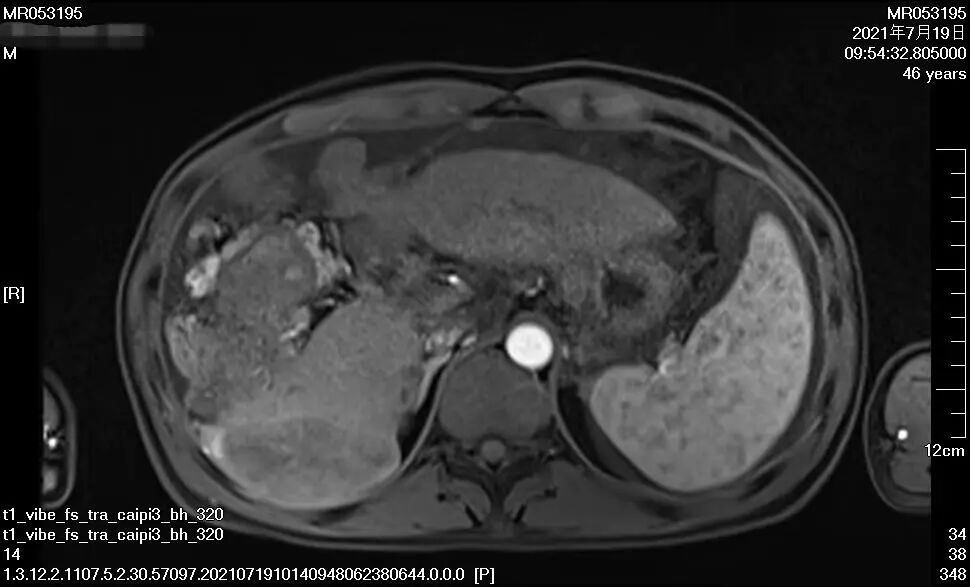

▲上圖1、2為馬先生接受治療兩月后

下圖3、4為馬先生接受治療一年后

經過整整一年的時間,16次靶向+免疫治療,近日,馬先生進行肝臟增強CT復查顯示,腫瘤相比一年前已經小了太多,“對于馬先生這種情況的肝癌患者而言,能取得這樣的療效真的是非常不容易,我們相信在接下來的進一步治療與馬先生自身積極態(tài)度下,一定能‘捷報頻傳’!”腫瘤二科主治醫(yī)師楊長命說。